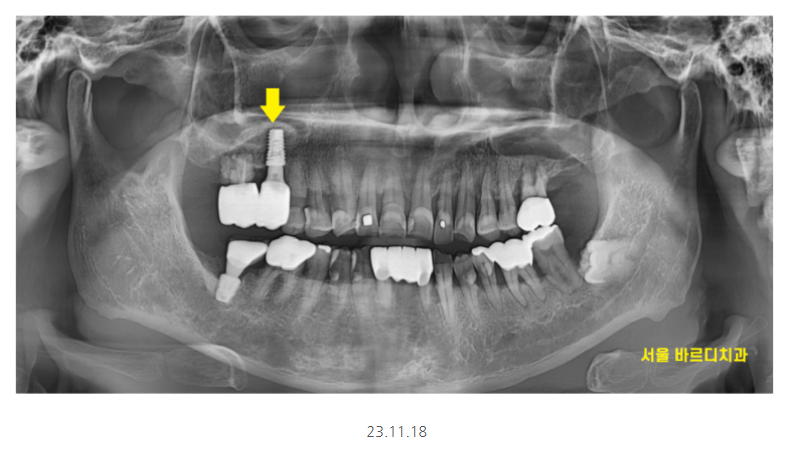

x-ray상에서 치석이 보일정도로

치석도 많고 잇몸관리가 안되고 계셨어요.

제일 불편을 호소한 치아 한개만 발치 후

임플란트를 진행했습니다.

강일동 임플란트가 완성되기까지

다른 부위 잇몸치료도 진행해드리고

관리해드렸습니다.